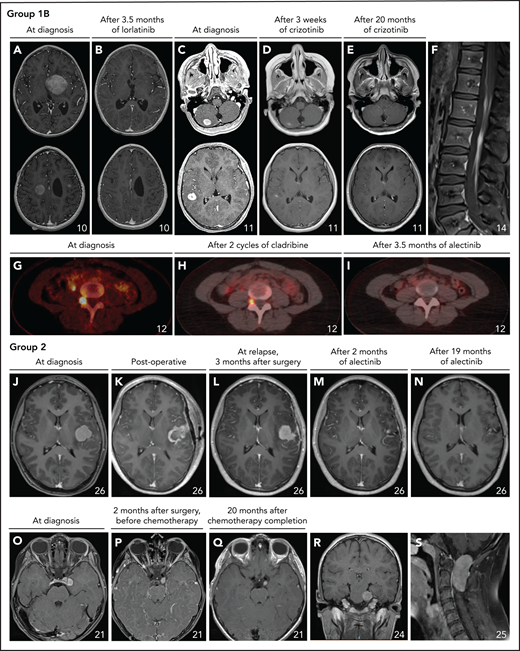

Neurologic involvement in ALK-positive histiocytosis patients from Group 1B or 2. (A-E) Axial images of the T1-weighted contrast-enhanced MRI scans of the heads of 2 pediatric cases with multiple solid brain tumors before and after treatment with ALK inhibition, demonstrating robust responses in both. (F) Sagittal image of the T1-weighted contrast-enhanced MRI scan of the spine showing leptomeningeal contrast enhancement along the descending cauda equina nerve roots. (G-I) Axial images of successive fluorodeoxyglucose PET-CT scans showing partial and complete response of a neuroforaminal tumor at level L5 after 2 cycles of cladribine (H) and subsequent treatment with alectinib (I), respectively. Coronal images (not shown) demonstrated that the tumor followed the course of the exiting nerves, highly reminiscent of nerve sheath tumors such as neurofibromas. (J-N) Axial images of successive T1-weighted contrast-enhanced MRI scans of the head of a child with a left insula tumor before and after subtotal resection and successful treatment with alectinib. (O-Q) Axial images of the T1-weighted contrast-enhanced MRI scans of the head of a child with a left oculomotor nerve tumor, demonstrating slight regression but continued contrast enhancement of the tumor after treatment with vinblastine/prednisone-based chemotherapy. (R) Coronal image of the T1-weighted contrast-enhanced MRI scan of the head showing a 30 × 25 × 34 mm large tumor with contrast enhancement in the prepontine cistern that followed the course of the trigeminal nerve and caused pressure on the pons. (S) Sagittal image of the T1-weighted contrast-enhanced MRI scan of the cervical spine showing a large (18 × 24 × 45 mm) intradural extramedullary tumor at level C1-C2.

Group 1B contained 5 children and 5 adults who presented with disseminated disease involving various organs (Table 1), including 3 infants without hematopoietic involvement. The most commonly involved organs were the nervous system (7/10), bone (7/10), lungs (7/10), liver (5/10), skin (4/10), and lymph nodes (4/10). All 3 pediatric cases with neurologic involvement had multiple masses in the brain (Figure 4A-E); adult cases had lesions of cranial and/or spinal nerves (3/4; Figure 4G-I), intramedullary spinal cord and/or leptomeningeal enhancement (2/4; Figure 4F), and/or parenchymal brain masses (1/4). Reminiscent of the localization of bone lesions in ECD, bone involvement included bilateral lesions in femora and/or tibiae in 7/7 patients (Figure 3A-D). Lung involvement was uniformly characterized by pulmonary nodules, ranging in size from micronodules to significant tumors (Figure 3H-K). All 5 patients with liver involvement had focal lesions on imaging.

Patients in Group 2 were 20 children and 3 adults, including 12 cases with neurologic involvement (52%). Patients with neurologic involvement presented with diverse neurological symptoms, including seizures (3/12), ataxia (3/12), headaches (3/12), vomiting (2/12), hypotonicity (2/12), unclear paroxysmal neurologic symptoms (“spells”) (1/12), torticollis (1/12), trigeminal neuralgia (1/12), paresis (1/12), and diplopia (1/12). Tumoral lesions were widely distributed in the central and peripheral nervous system (Figure 4J-S; Table 3). In addition, 2 patients had cerebrospinal fluid monocytosis, including 1 case with a very low level of ALK rearrangements in the cerebrospinal fluid by FISH analysis. The 11 patients with nonneurologic disease comprised 1 case with a single lung tumor, 2 cases with solitary bone lesions, and 8 children with localized skin lesions or soft tissue tumors in varying locations (Figure 5; Table 3).